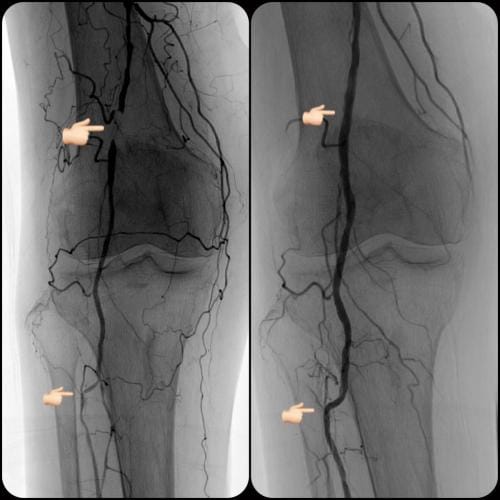

- What is the experience? Choose a specialist that has a proven record of tackling difficult cases successfully. Some specialist choose to only do the simple procedures and refer the rest to surgery. Additionally, if the specialist can only perform simple procedures they may have a higher rate of complication if the case turns out to be more difficult than expected. Our specialist has performed numerous successful complex procedures from the groin, knee and foot. See our prior cases here.

During these procedures: Sedation is given to help you relax. Next, a tiny tube is gently inserted in an artery, usually in the groin or upper thigh area. You will be given a local anesthetic to numb the area where the tube will be inserted. It is then guided through the blood vessel toward the disease artery. When it’s in place, a dye is injected through the catheter to visualize the arteries. An X-ray is taken to help the physician pinpoint the area that is blocked or narrowed. The physician then uses tiny wires and catheters to get through the diseased vessels. Depending on the images treatment may then be performed.

Angioplasty — a special catheter that has a balloon on one end is advanced into the diseased artery. This is temporarily inserted through the narrowed artery and inflated to flatten the plaque against the artery wall, opening the artery and restoring blood flow.

Stent placement —a stent is a small, expandable, leg pain angioplasty stent los Angeles san diegomesh-like tube that supports the artery and helps to keep it open. Implanting a stent does not require open surgery. The doctor inserts a catheter into an artery in your arm or leg, similar to the balloon angioplasty procedure. A specially designed catheter delivers the stent to the narrow area in the artery. The stent is expanded, flattening the plaque against the artery wall and holding the artery open with a mesh tube. The catheter used to deliver the stent is then removed, but the stent stays in your artery permanently to maintain healthy blood flow.

Atherectomy — a specialized catheter that modifies the plaque in the arteries. Unlike angioplasty and stenting, which are designed to move plaque to the sides, atherectomy involves cutting and removing or sanding down the plaque from the artery, restoring normal blood flow.